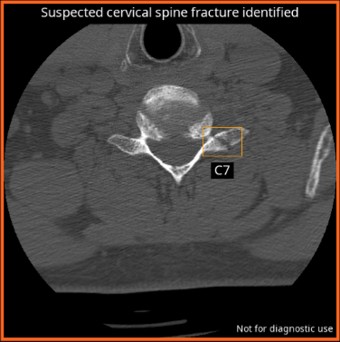

CINA Cspine (FDA)

CINA-CSpine is an AI triage tool that detects acute cervical spine fractures, including those with non-displaced fracture lines and/or displaced fracture fragments on non-enhanced neck CT scans.